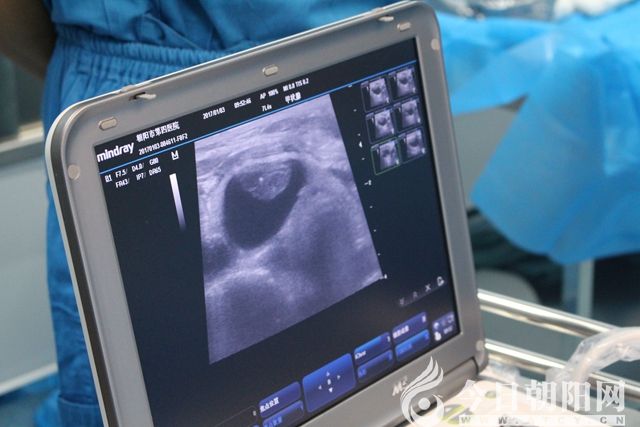

術(shù)前超聲定位

微波消融針穿刺至實(shí)性病變處,根據(jù)超聲引導(dǎo),調(diào)整消融針,連續(xù)消融,至病變區(qū)域全部達(dá)到熱容效應(yīng)?;颊咴谑中g(shù)中始終保持清醒,無(wú)明顯疼痛等不適感,偶有咽喉部輕度的腫脹感。術(shù)后4小時(shí),患者離床活動(dòng),飲水無(wú)嗆咳,聲音無(wú)嘶啞。術(shù)后第3天,患者恢復(fù)良好,現(xiàn)已出院。